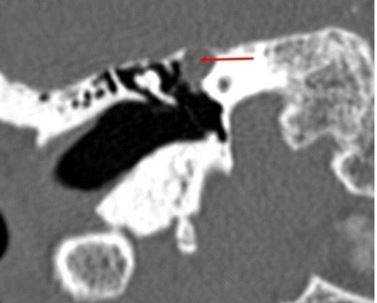

КТ (А) и МРТ(В) - картина холестериновой гранулемы

Эта дилемма волнует многих пациентов, но вид исследования выбирает лечащий врач, опираясь на результаты предыдущей диагностики и на конкретные жалобы. Отказываться от КТ уха из-за ложных соображений о вреде процедуры не стоит, современные мультидетекторные томографы позволяют минимизировать влияние лучевой нагрузки для большей категории лиц (исключение - беременные и дети, не достигшие 14 лет). В ряде наблюдений, особенно, если визуализируется опухолевый процесс, может понадобиться и МРТ, и КТ уха - эти способы взаимодополняют друг друга. Выполнение магнитно-резонансного сканирования обосновано, если после проведенной КТ остались сомнения в диагнозе. МРТ лучше демонстрирует менингоцеле, холестеатому, неврит лицевого нерва, внутричерепную патологию, вызванную процессами в среднем ухе, что не всегда показывает компьютерная томография высокого разрешения. КТ среднего уха часто не способна визуализировать степень возможной облитерации улитки после перенесенного воспаления или отдаленные последствия перелома височной кости. Точная оценка состояния имеет решающее значение для планирования кохлеарной имплантации.